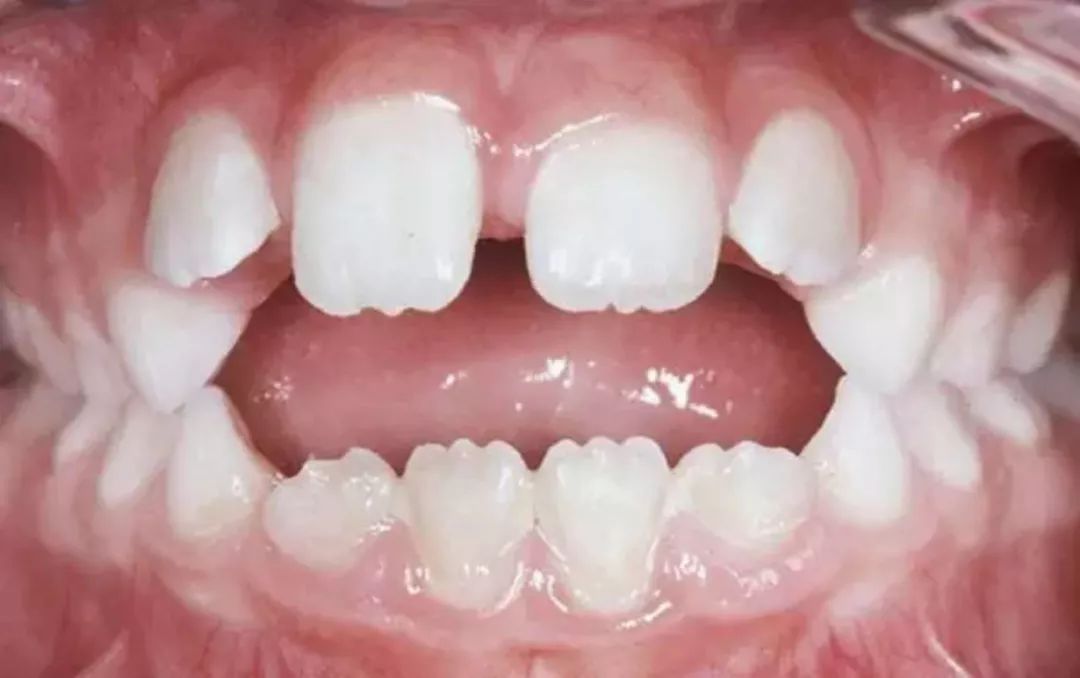

同时,口呼吸时,舌会卧于下颌前牙上,影响前牙垂直向发育,会导致前牙开合。据统计,3-6岁儿童中,口呼吸和前牙开合的关联率为35.5%(美国,2008)。

前牙开合